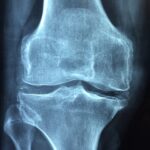

Ist der Harnsäurewert im Blut dauerhaft erhöht, kann dies zu einem Gichtanfall führen. Er ist ein Zeichen dafür, dass sich Harnsäurekristalle im Gelenk angesammelt und zu einer schmerzhaften Entzündung geführt haben. Bei den Gelenken sind meistens Füße oder Hände betroffen. Die Harnsäurekristalle lösen dort eine Entzündung aus, wodurch die Gelenke anschwellen, warm werden und schmerzen. Die Entzündung klingt in der Regel innerhalb von ein bis zwei Wochen ab. 2,3,17

Ein hoher Harnsäurespiegel führt jedoch nicht zwangsläufig zur Gicht, sondern erhöht lediglich das Risiko. Dies mag daran liegen, dass andere Faktoren hinzukommen müssen. So wurde festgestellt, dass sich die Harnsäurekristalle vor allem dann in den Gelenken bilden, wenn sie zu wenig Gelenkflüssigkeit haben. Auch der pH-Wert der Gelenkflüssigkeit und die Temperatur des Gelenks spielen eine Rolle. Die Menge der Gelenkflüssigkeit hängt übrigens mit der täglichen Flüssigkeitszufuhr zusammen. Auf diese Weise können sich Harnsäurekristalle auch in den Nieren ablagern (Uratnephropathie). Gemäß IQWiG bestehen 5 bis 10% der Nierensteine aus Harnsäure.3,8,18–21

Für die langfristige Gesundheit stellen erhöhte Harnsäurewerte durchaus eine Gefahr dar. Immerhin können Gichtanfälle zu einer chronischen Gicht führen, wodurch die Gelenke geschädigt und in der Folge die Muskeln geschwächt und die Beweglichkeit eingeschränkt werden.

Liegen Schmerzen und Schwellungen in den Gelenken vor, die ein bis zwei Wochen anhalten, sollte nach Abklingen der Beschwerden beim Hausarzt der Harnsäurewert mittels Blutanalyse untersucht werden. Misst man den Harnsäurespiegel während eines akuten Anfalls, kann es sein, dass der Wert im Blut normal ist. Für die sichere Diagnosestellung muss das Gelenk punktiert werden, um die Harnsäurekristalle im Gelenk nachweisen zu können. In vielen Fällen begnügt man sich jedoch auch damit, anhand des erhöhten Harnsäurespiegels und des Beschwerdebildes die Diagnose zu stellen.2,3